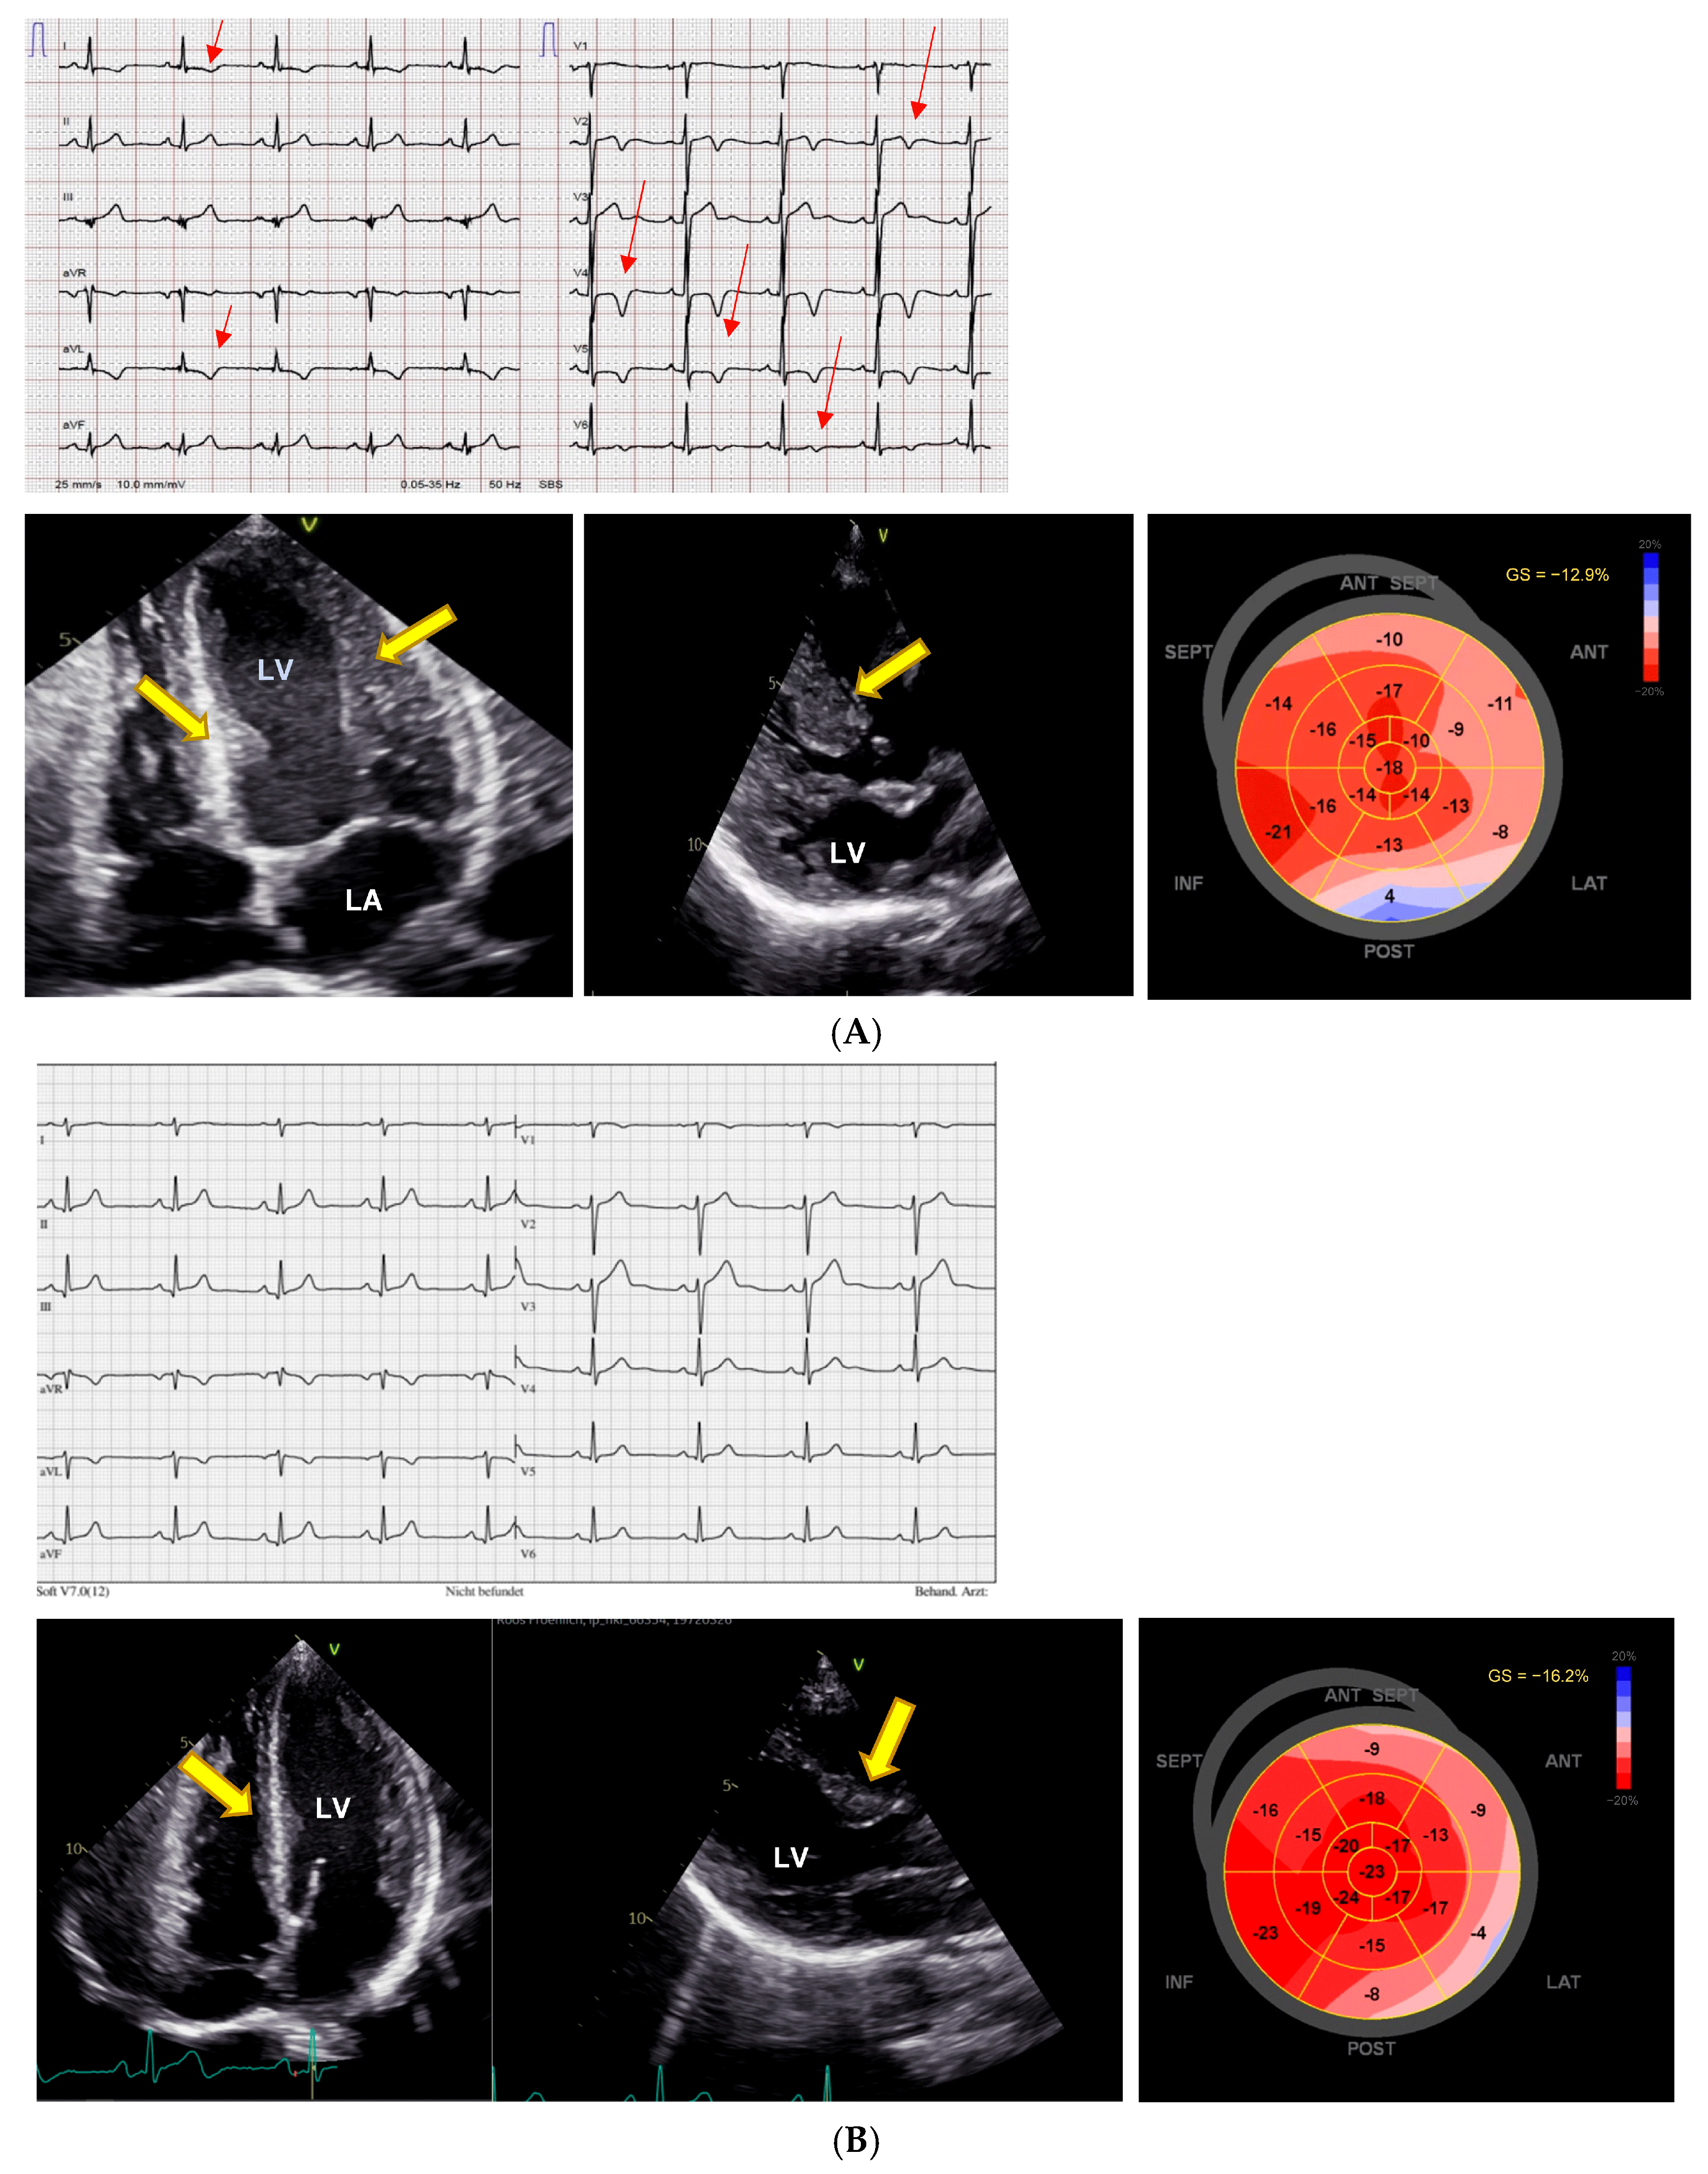

NT-proBNP was 226 ng/L (normal < 121 ng/L), there were no signs of pheochromocytoma, and renal function was normal. She had no cardiac symptoms, but there were ECG changes (Figure 2A), and transthoracic echocardiography revealed pronounced LVH and severe reduction in the LV GLS to −13%. A pharmacogenetic investigation found a CYP2D6 intermediate metabolizer phenotype (AS 1.0, genotype *1/*4.001) IM, and CYP2C19 ultrarapid metabolizer phenotype (genotype *17/*17). VEN dose was reduced to 37.5 mg/day as the patient refused to stop it completely, and under the reduced dose serum concentrations were low-normal (VEN 0.12 µmol/L; O-desmethyl-VEN 0.31 µmol/L, and VEN + O-desmethyl-VEN 0.43 µmol/L (normal 0.36–1.44 µmol/L)). Subsequently, the ECG normalized, and echocardiographic abnormalities regressed (Figure 2B). Cardiac evaluation in November 2024 under Venlafaxine 75 mg shows regression of LV-hypertrophy (yellow arrows), a LVEF of 54%, and an improvement in the LV strain (−16.2%).

Figure 2.

Reversible hypertrophic cardiomyopathy after dose reduction. (A) ECG and echocardiography with pronounced changes resembling hypertrophic cardiomyopathy. First cardiac evaluation, May 2023. The ECG shows normal sinus rhythm with a QTc interval of 455ms and negative T-waves resembling HCM (red arrows). Transthoracic echocardiography during therapy with venlafaxine 150 mg shows severe left ventricular hypertrophy (yellow arrows) with a preserved left ventricular ejection fraction of 60%, and a severely diminished left ventricular global longitudinal strain of −12.9%. LV = left ventricle, LA = left atrium. (B) Reversal of ECG changes and regression left ventricular hypertrophy (yellow arrows) after 1.5 years as well as improvement of left ventricular global longitudinal strain to −16.2%.